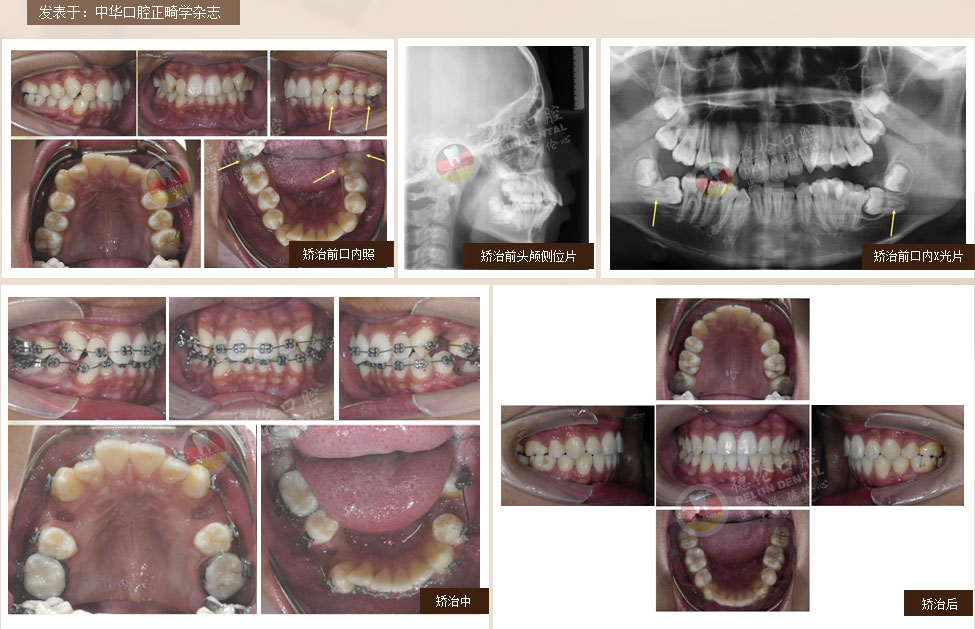

• 男:17岁

症状:下颌右侧第二、第三磨牙水平阻生,下颌左侧第三磨牙水平阻生

矫治方法:下颌拔除两颗第三磨牙(智慧齿)